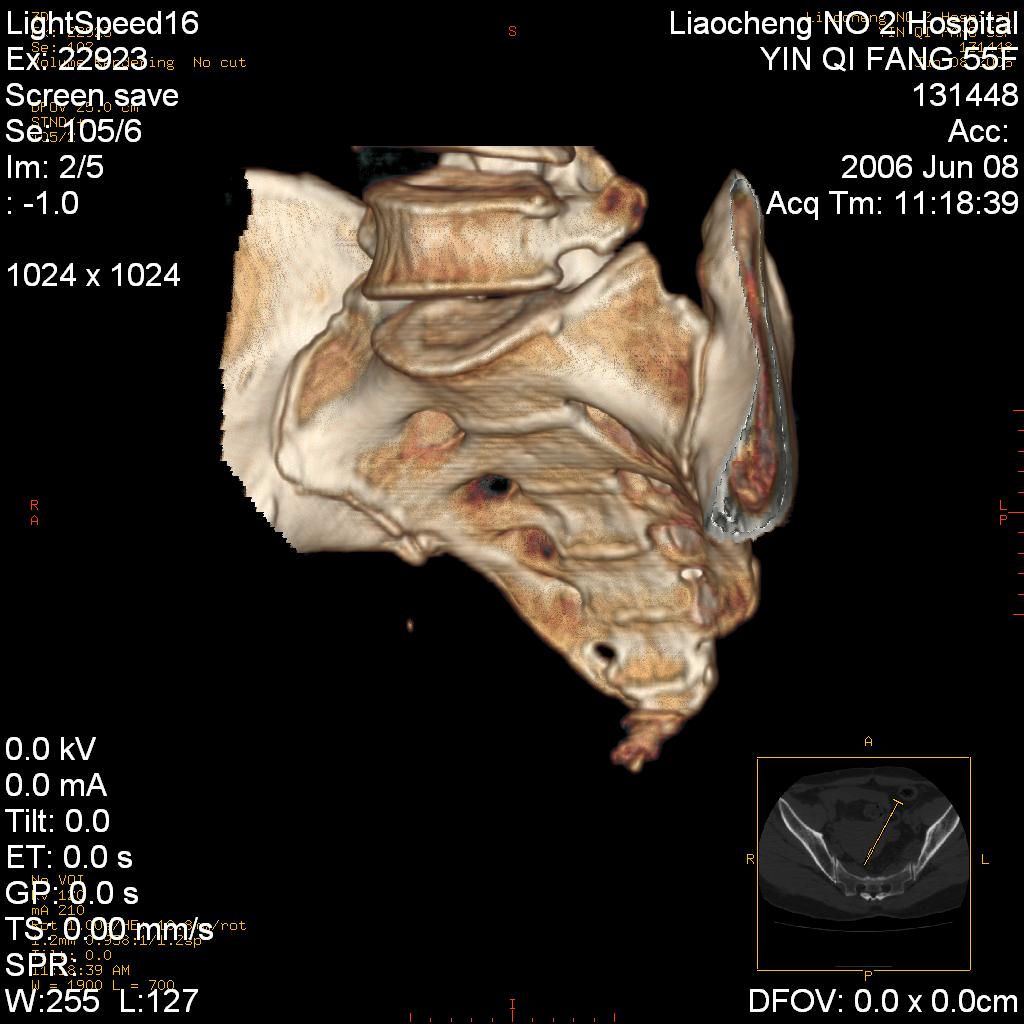

女,55岁,十余年前骶尾骨摔伤,x线平片诊断骶骨裂纹骨折,现在骶尾部又疼痛2月,x线怀疑骶骨左下部骨质破坏。大家看看,是不是先天变异。正常人不是只有4个骶孔吗?怎么此病例有5个?

三维做的不错,好像没什么病。

dg 三维很好,佩服

两侧骶髂关节炎,确实做得很漂亮

众口一词啊,图象确实漂亮,羡煞人也!右侧骶髂关节间隙变窄,相对缘增生硬化,髂骨侧增生明显。左侧轻微类似改变,考虑双侧骶髂关节炎。余未见异常。

考虑双侧骶髂关节炎。余未见异常。

图像确实漂亮,骶髂关节及骶尾椎均未见异常。

支持骶髂关节炎,3d做得很漂亮!!!!

三维作的很漂亮,真羡慕。